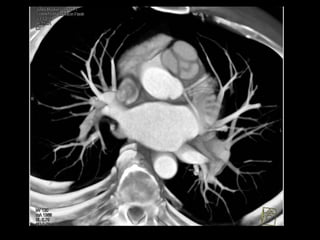

Ressonância magnética

Além de medir o diâmetro da artéria pulmonar:

Pode visualizar a direção e a velocidade do fluxo

sanguíneo nas câmaras cardíacas e nos grandes

vasos, obtendo imagens precisas das estruturas

cardiovasculares;

Técnica de escolha em longos seguimentos;

Diagnóstico de hipertrofia do VD e dilatação das

artérias pulmonares;

RM normal de tórax